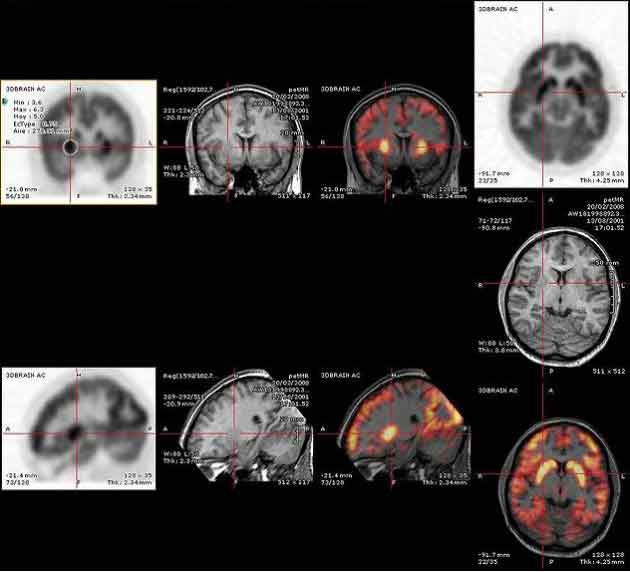

L’immagine PET mostra l’attivazione delle aree cerebrali coinvolte nel risveglio dall’anestesia. A sinistra, le sezioni sagittale (sopra) e assiale (sotto) mostrano l’attivazione della corteccia cingolata anteriore, del talamo e dell’area del locus coeruleus e del nucleo parabrachiale del tronco encefalico. A destra, le immagini dell’attivazione corticale non mostrano alcuna attivazione evidente.

Il risveglio dall’anestesia è spesso associato a una fase iniziale di turbamento e di delirio prima del pieno recupero della coscienza e della consapevolezza dell’ambiente circostante. Utilizzando tecniche di imaging cerebrale su volontari sani, un team di ricercatori coordinati da Harry Scheinin, dell’Università di Turku, in Finlandia, in collaborazione con i colleghi dell’Università della California a Irvine, hanno ora scoperto il perché, evidenziando il processo di ritorno alla coscienza dopo l’anestesia generale. L’emergere della coscienza è infatti risultato associato all’attivazione di strutture cerebrali profonde e primitive anziché della neocorteccia, più giovane dal punto di vista evolutivo.

Per arrivare a questa conclusione, sono stati sottoposti a scansione cerebrale 20 volontari anestetizzati con i farmaci dexmedetomidina o propofol. I soggetti venivano poi svegliati e i cambiamenti nell’attività cerebrale catturati in immagini mediante la tecnica di tomografia a emissione di positroni (PET).